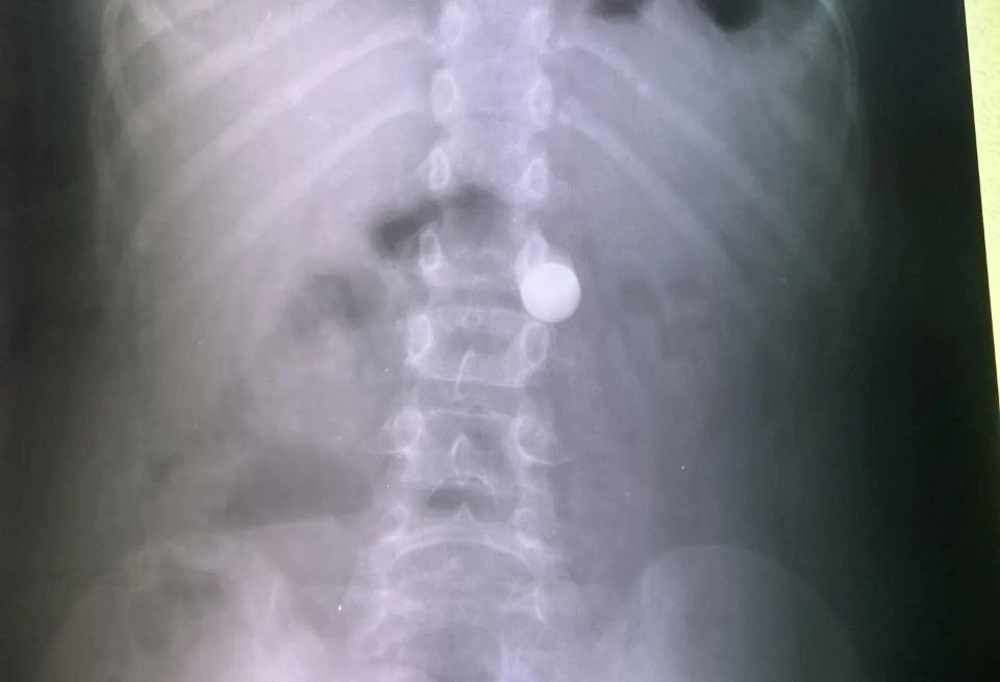

Как сообщил телеграм-канал медицинского учреждения, январь 2026 года приятно удивил врачей-эндоскопистов. Обычно в период каникул в больницу регулярно поступают маленькие пациенты с проглоченными монетами, косточками или деталями конструктора. В этот раз за все праздничные дни врачи столкнулись лишь с одним подобным случаем: в отделение привезли восьмилетнего мальчика, который проглотил массивный металлический шарик диаметром в сантиметр.